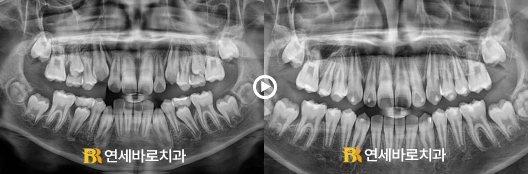

[영구치 맹출장애 케이스] 송곳니 맹출공간 소실되고 배열이 한쪽으로 쏠려서 중심선이 불일치하여 인비절라인 퍼스트로 맹출공간 확보 및 치열을 개선했습니다